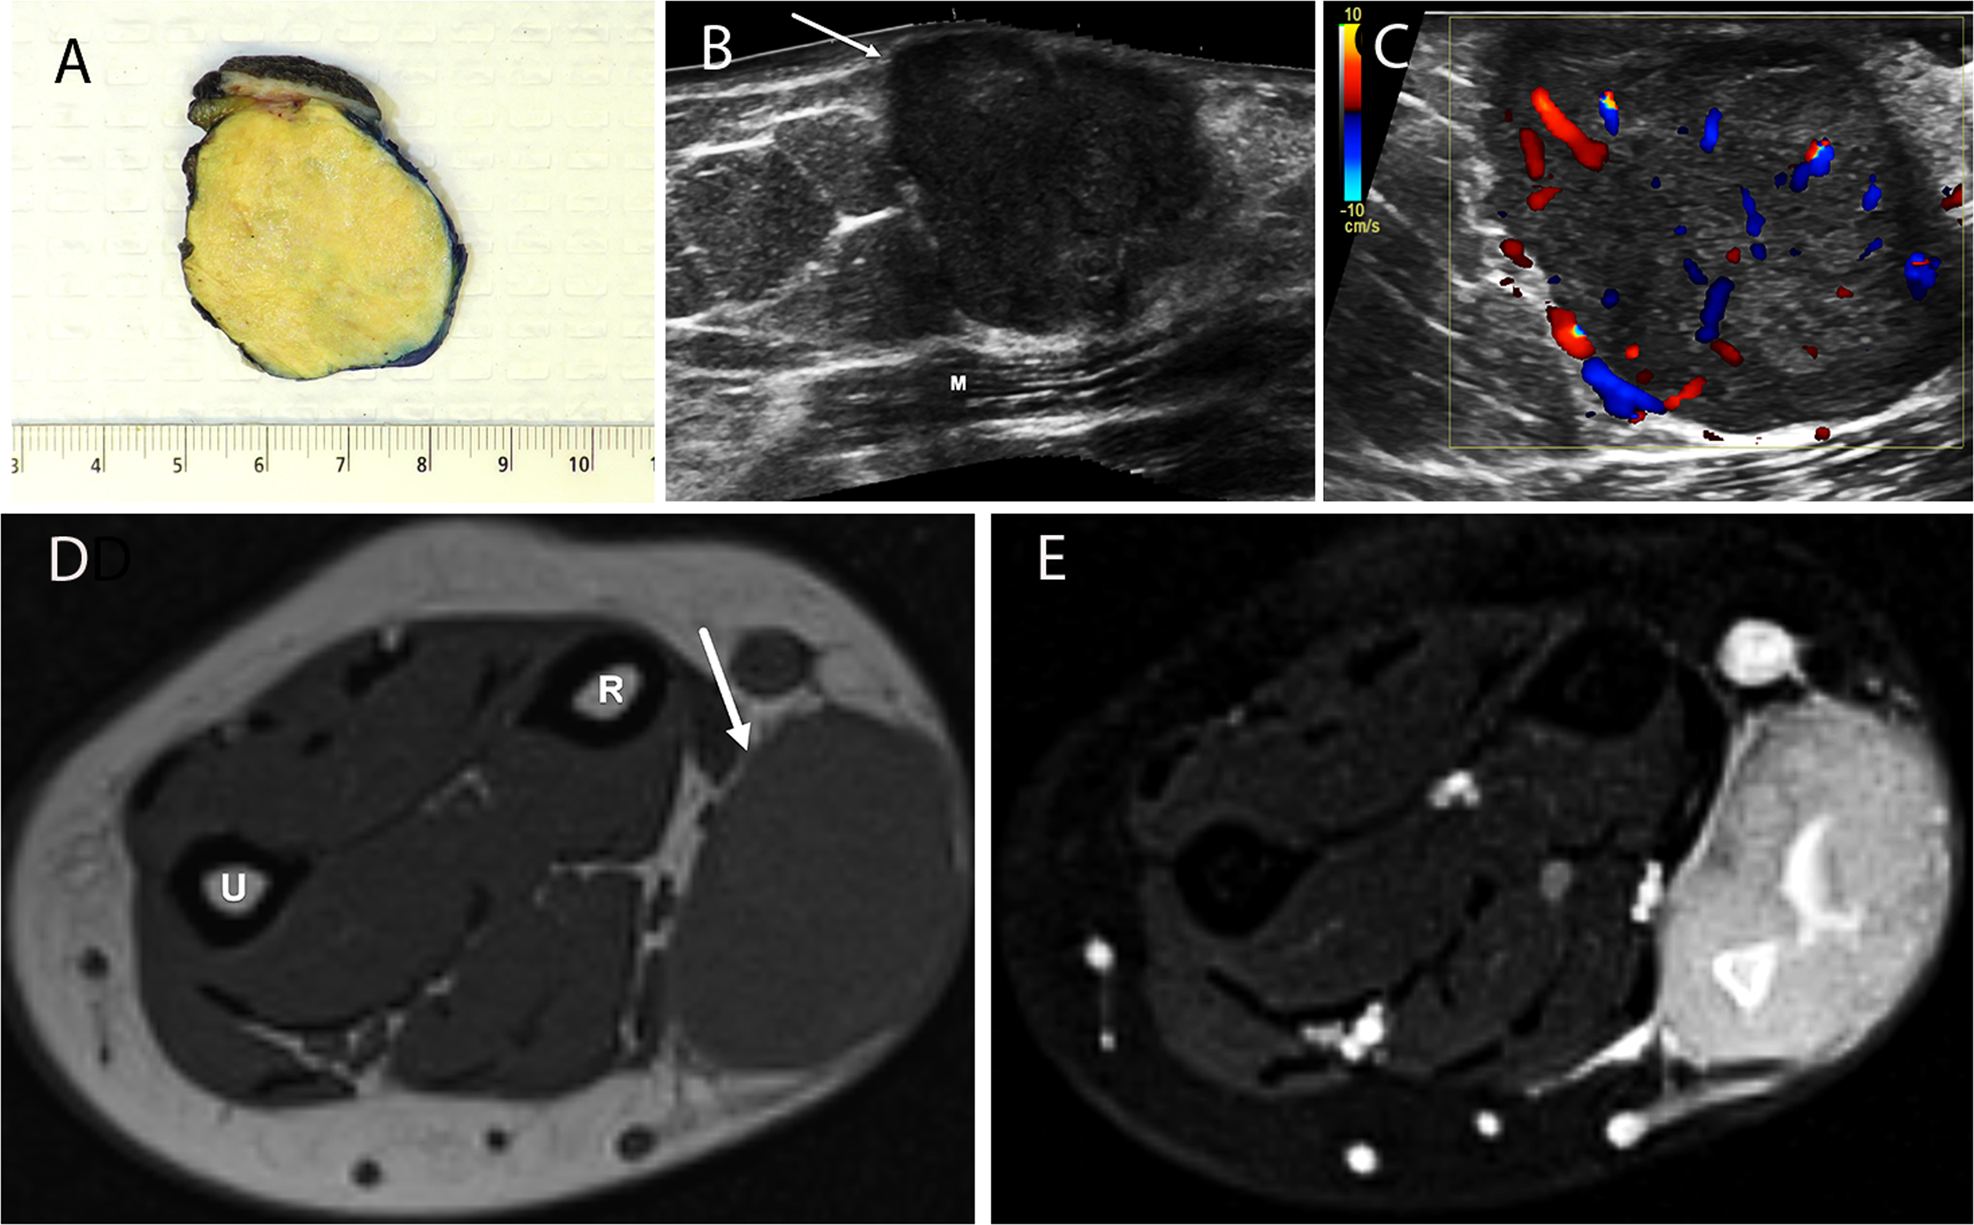

Xanthogranulomatous epithelial tumors and keratin-positive giant cell-rich  soft tissue tumors: two aspects of a single entity with frequent  HMGA2-NCOR2 fusions | Modern Pathology, image size:1974x1225

Xanthogranulomatous epithelial tumors and keratin-positive giant cell-rich soft tissue tumors: two aspects of a single entity with frequent HMGA2-NCOR2 fusions | Modern Pathology

Xanthogranulomatous epithelial tumors and keratin-positive giant cell-rich  soft tissue tumors: two aspects of a single entity with frequent  HMGA2-NCOR2 fusions | Modern Pathology, image size:1200x701

Xanthogranulomatous epithelial tumors and keratin-positive giant cell-rich  soft tissue tumors: two aspects of a single entity with frequent  HMGA2-NCOR2 fusions - Modern Pathology, image size:1494x1185

Xanthogranulomatous epithelial tumors and keratin-positive giant cell-rich soft tissue tumors: two aspects of a single entity with frequent HMGA2-NCOR2 fusions - Modern Pathology